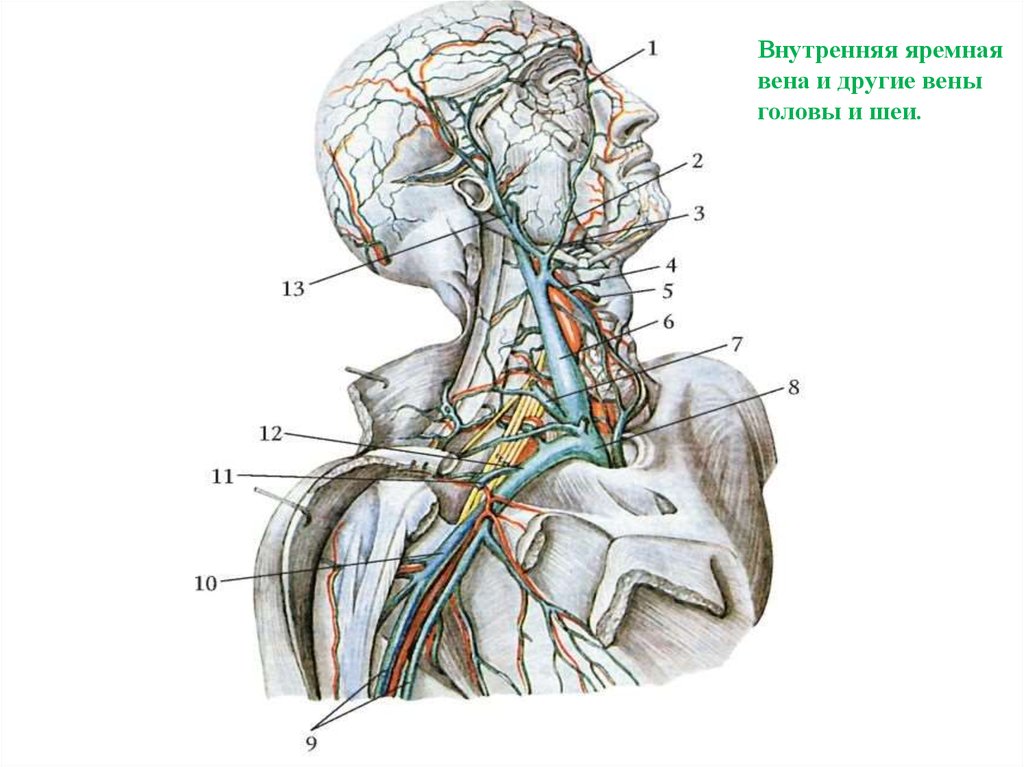

Анатомия внутренней яремной вены: КТ изображения